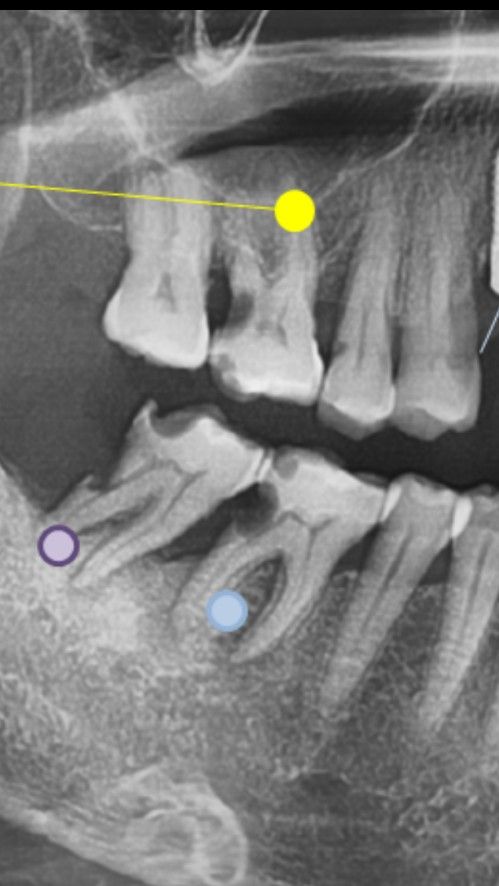

뼈이식 상악동 거상술 통해 꼭 진행 해야하나요?

한곳은 상악동 거상술후 뼈이식 3개 권유하셨고

한곳은 3개다 뼈이식 불필요 상악동거상술 불필요

추후 뼈이식 혹시 한개 할수도 있다

다른곳 뼈이식 1개는 해야한다

별다른 언급없음 치료 시작해봐야 안다

해당 치아는 파노라마 사진 상에서는 뼈이식을 반드시 해야 하는 부위입니다. 뼈이식을 권하지 않았던 치과도 술식 도중에 뼈이식을 추가할 가능성이 있습니다. 즉 이는 뼈이식을 하지 않고 단순히 시술하는데 있어 무리가 따르게 되고 임플란트의 충분한 고정력이 나오지 않을 수 있습니다. 안전하게 시술하기 위해서는 상악동거상술을 하는 것이 필요한 부위입니다.

상악동 거상이 필요할수도 잇고 없을수도 잇을것같습니다. 짧은 임플란트를 심는다면 상악동 거상술은 필요하지 않고, 조금더 긴 임플란트를 심는다면 거상술이 필요할꺼 같으며 뼈이식을 하지 않아도 임플란트를 할수 있을것같습니다.